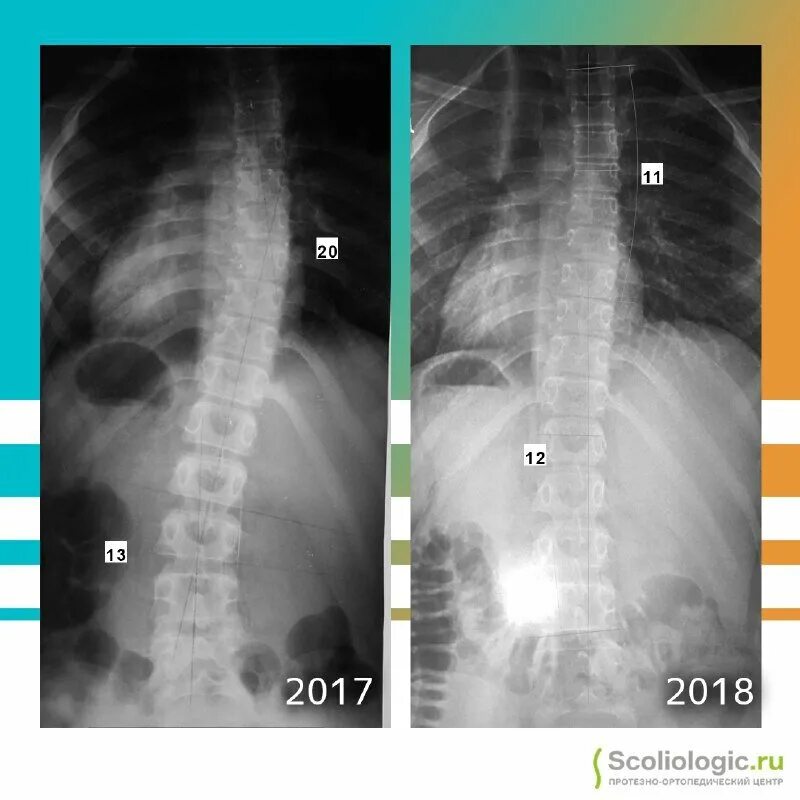

Дуга 37 градусов